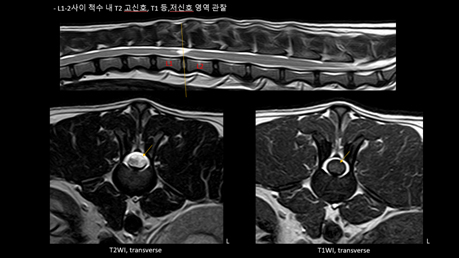

봉이는 MRI검사 결과 척수에 염증이 발생하여 주변 신경이 손상되는 척수염이었다. 척수에 발생하는 염증이 광범위해질 경우 생명을 잃을 수 도 있는 매우 심각한 상황이었지만, 봉이는 다행히 국소적인 척수 손상에 의해 하반신 마비가 발생한 상황이었다.